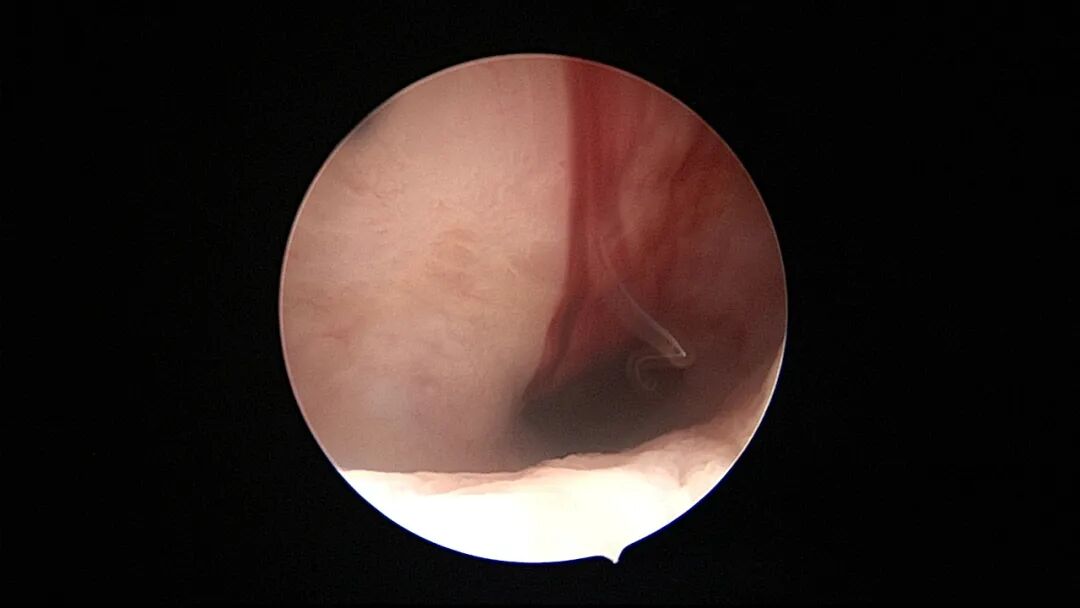

病例2:36岁,G4P2,剖宫产2次。异常子宫出血5年,主要为月经干净半个月左右少许出血,月经周期第14天B超内膜厚0.6cm(双层)。月经周期第18天宫腔镜探查,内膜平滑,见腺体开口,病检为增殖期样子宫内膜。

| ||||